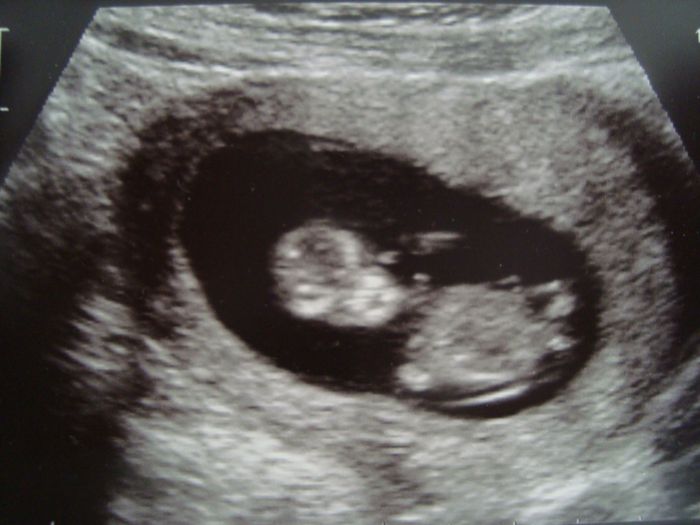

Po probdele noci jsme s pritelem dorazili v nervech k ordinaci. Pribehla porodni asistentka, ze jestli jdeme na prvo.trim.scr, ze udelame rychly uzv, aby ty data mohli zadat k odberum. Mojeho hned vtahla dovnitr a byla to fakt rychlovka. Ale za tu rychlovku je vysledek, ze z jeji strany to vypada dobre. A ted jsme opravdu trhli rekord. Stari dle PM 10+5 ,ale pozor, dle uzv 11+4 a velikost 48,4 mm! Prikladam fotecky -zepredu jako mimozemstanek, z boku mimonko, ktere mava. A fakt na tom uzv mavalo! Normalne jsem slysela, jak priteli spadnul kamen ze srdce a cekala jsem, kdy spadne ze zidle. Ze mi brali ctyri obr zkumavky mi uz bylo jedno. Ted jeste vydrzet na imuno vysledky a bude dobre. Takze holky, kdyz to tak jde nam po tech problemech, tak to dobre dopadne i vam.

Aro no nádhera...a krásné fotečky